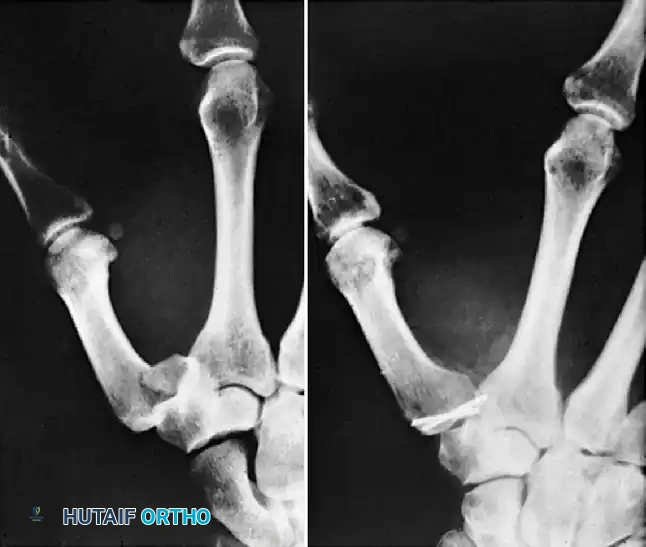

Figure 1: Displaced, unstable condylar fracture. The articular step-off and rotational deformity necessitate intervention to restore joint congruity.

Figure 2: Manipulation of the fracture using the intact collateral ligament. This tension permits the precise insertion of a Kirschner wire to provisionally hold the reduction.